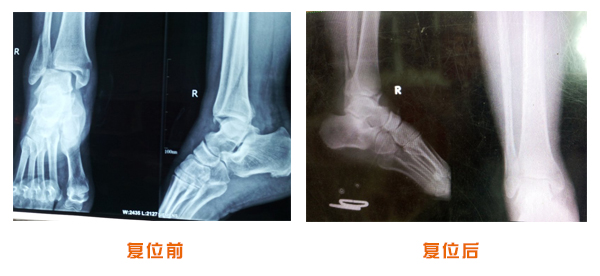

尺橈骨克雷氏骨折治療前后